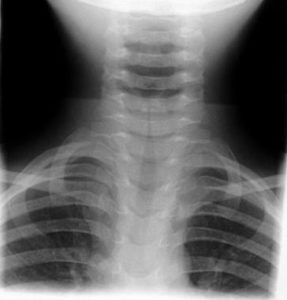

Identify

Which of the age groups are most at risk for having the fracture type shown in this picture

Concerning this picture which is incorrect

What fracture type is identified in the radiograph: